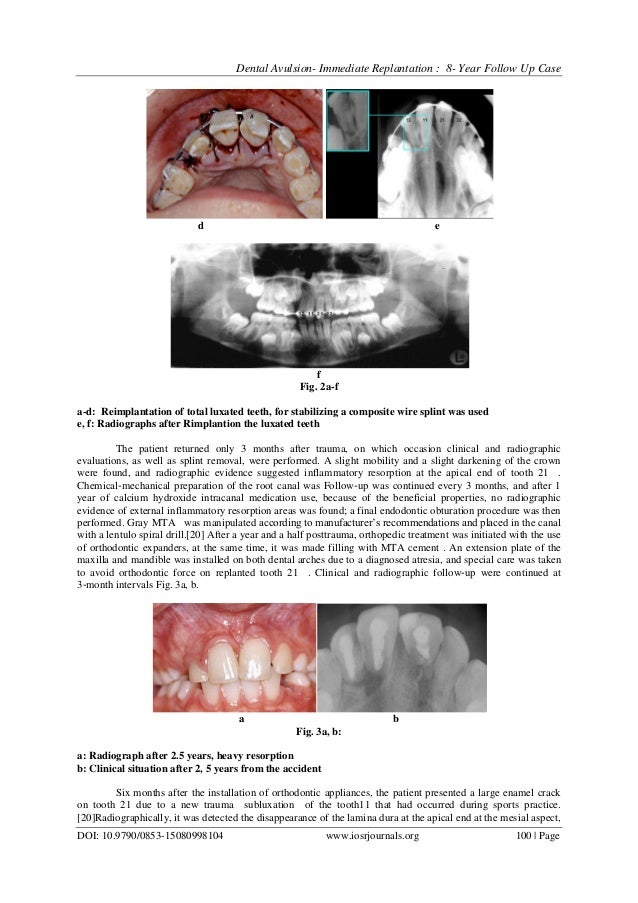

Dental avulsion immediate replantation Orthodontic Treatment After Avulsion Is to delineate an approach for the immediate orurgent care of avulsed permanent teeth. Endodontic treatment should always be undertaken after isolation with the dental dam. Adjunctive orthodontic treatment is subdivided into those interventions that can be used at or near the time of the trauma, those available for longer posttrauma treatment, and. The definitive treatment for the fractured crown. Orthodontic Treatment After Avulsion.